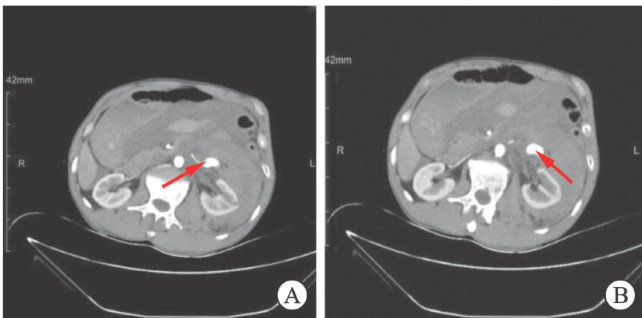

Rupture and hemorrhage of pseudoaneurysm in the left pararenal artery:a case report and literature review

左侧副肾动脉假性动脉瘤破裂出血1例报告并文献复习